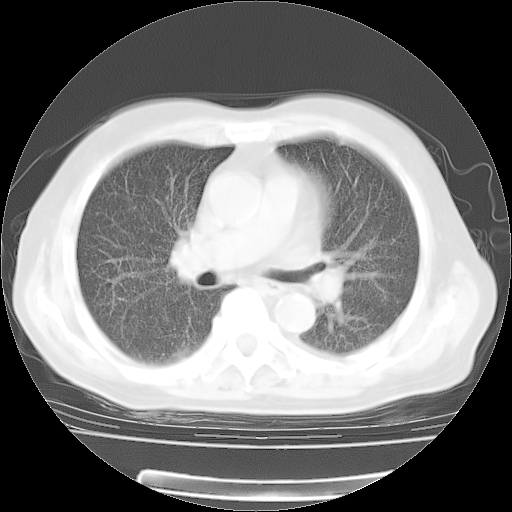

4月28日肺部CT——再次出现类似去年5月9日——透光度降低,“间质性”改变。

4月28日肺部CT——再次出现类似去年5月9日——磨玻璃样、间有“粟粒样”改变。

4月28日肺部CT